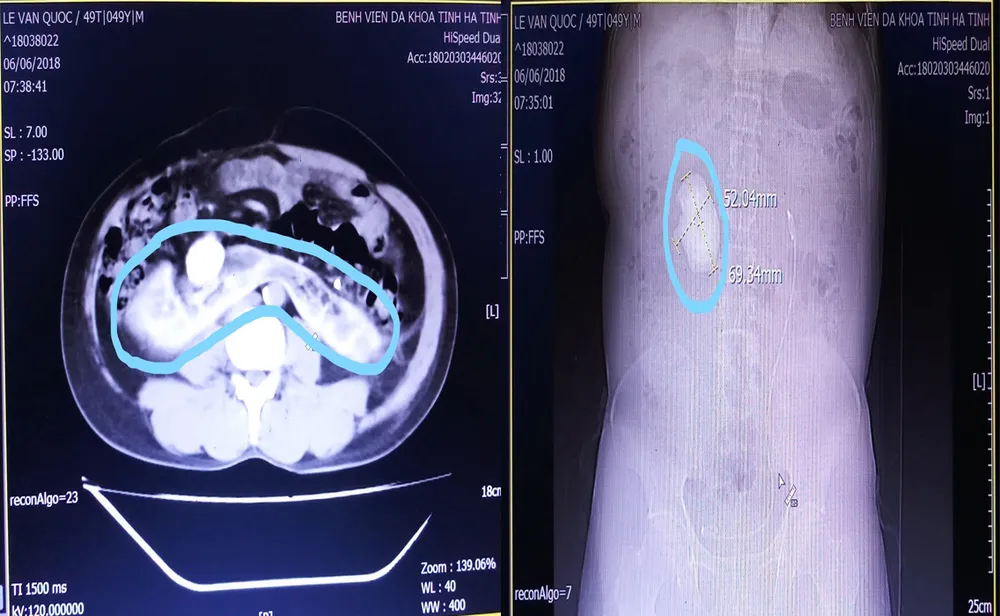

Trước đó, anh Lê Văn Q., có xuất hiện đau nhiều hai bên hông, đi tiểu buốt... được người nhà đưa vào BVĐK huyện Đức Thọ thăm khám. Tại đây, sau khi  chụp X quang và làm các xét nghiệm, các bác sĩ đã phát hiện khối sỏi to nên đã cho bệnh nhân chuyển lên BVĐK tỉnh Hà Tĩnh. Tại đây, sau khi làm các xét nghiệm cần thiết, đồng thời cho chụp CT đã phát hiện thận của bệnh nhân Q., ứ nước, có khối sỏi thận “khủng” bên phải, hình ảnh cho thấy hai trái thận của bệnh nhân dính nhau vùng cực dưới, điển hình của thận móng ngựa, khối sỏi thận phải có kích thước 69,34mm x 52,04mm.

Phẫu thuật lấy sỏi thận “khủng” trên bệnh nhân thận móng ngựa ảnh 2 Hình ảnh thận móng ngựa qua chụp cắt lớp (ảnh trái), hình ảnh sỏi thận "khủng" qua chụp CT (ảnh phải)